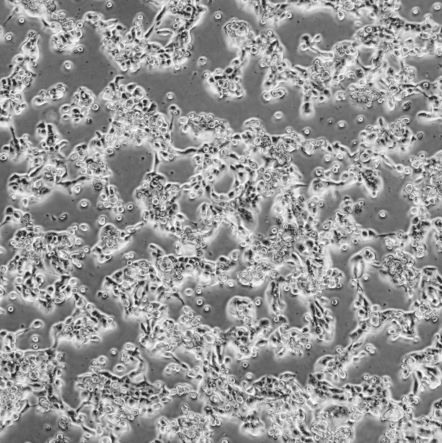

SNU-1411_人直肠腺癌细胞

细胞名称:SNU-1411_人直肠腺癌细胞

细胞形态:上皮样

培养条件:RPMI 1640 + 10% h.i. fetal bovine serum (FBS)

37 ℃, 5% CO2